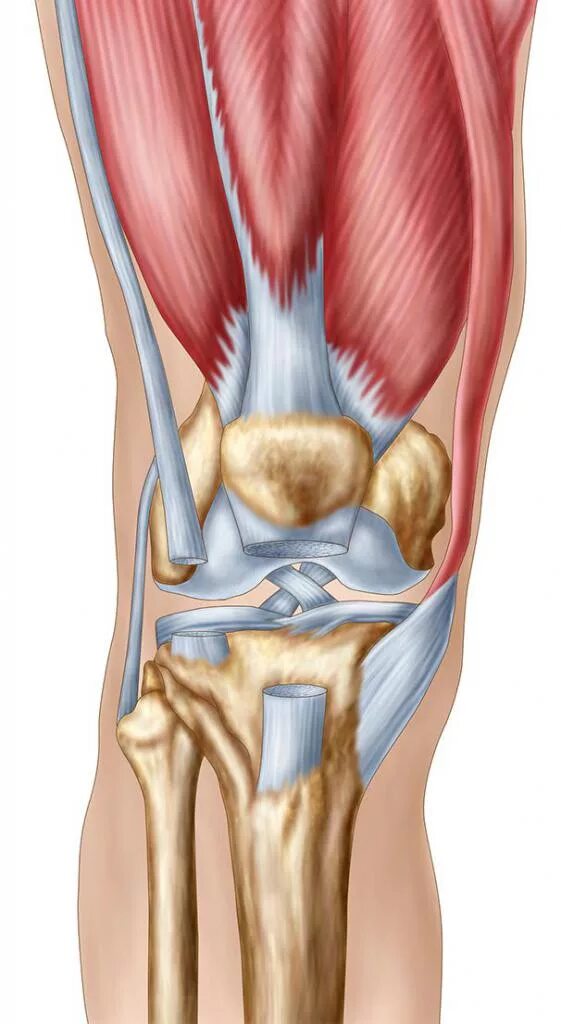

Как выглядит коленного